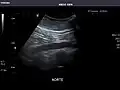

It can be used on the abdominal aorta to detect or exclude abdominal aortic aneurysm. For this purpose, the standard aortic measurement for abdominal aortic aneurysm is between the outer margins of the aortic wall.[4]

Aorta: Visualized portions normal in caliber, 16 x 15 mm.

Aorta -